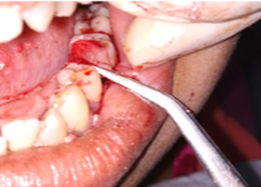

Placement of PRF Membrane